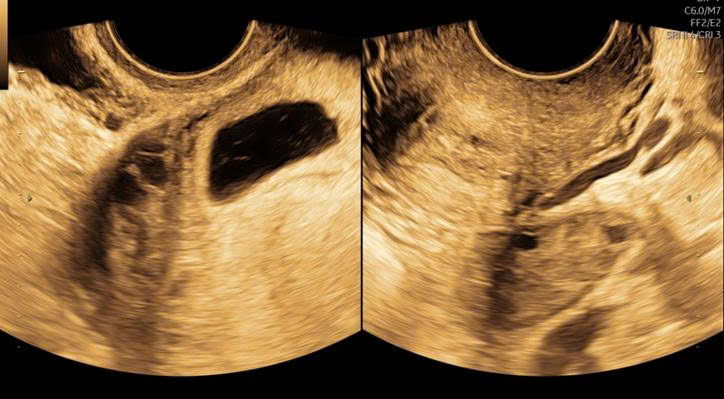

Ấy vậy mà kết quả siêu âm lại khiến chị H. 36 tuổi đã trải qua 2 lần sinh mổ không khỏi bàng hoàng: trong lòng tử cung không thấy thai, nhưng ngay vết sẹo mổ cũ trước đây lại xuất hiện một túi thai có tim thai 6,5 tuần.

Đó là một dạng thai bám vết sẹo mổ cũ – một thể đặc biệt của thai ngoài tử cung. Nghe qua thì nhẹ, nhưng thực tế lại vô cùng nguy hiểm vì thai có thể ăn sâu vào vết sẹo, gây vỡ tử cung hoặc chảy máu ồ ạt khi thai lớn lên, thậm chí đe dọa tính mạng và có nguy cơ không giữ được tử cung.

Hình siêu âm